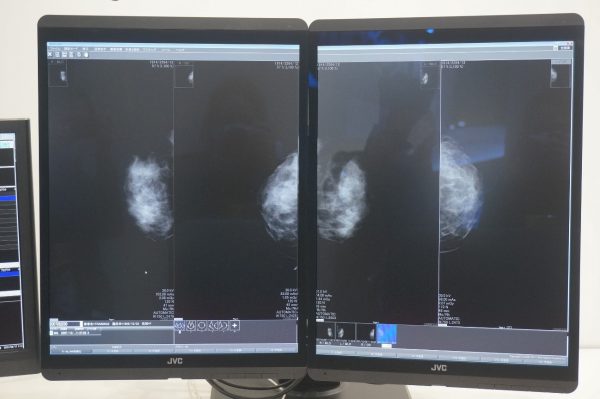

CL-S500 Dualstand

500万画素医用画像表示モニター2画面をデュアルスタンドで一体化したことにより、画面の高さ、上下と左右の角度を2画面同時に調整できる。左右それぞれの画面をユーザーが最も見やすい位置に調整することで、最適な輝度・コントラスト・色調を常に保てる。

同解像度の従来機種2台を並列した場合と比べて、スタンドベースの面積比を46%削減し、机上のデッドスペースが減る分、空間が広く使え、作業スペースが拡大。

また、ガラスフィルターに最新のAR処理を施すことにより、外光反射を大幅に抑制し、モニター本来が有する高解像度かつ高コントラストな画像を忠実に再現が可能に。硬度の高いガラスを採用することにより、モニター表面の美しさを保ちながら不意の衝撃・キズ・汚れから大切なモニターを守ることが可能。

こちらも、CL-S1200と同様、モニターに内蔵されたReading Lightで手元にあるキーボードやマウスを照らし、作業をサポートする。